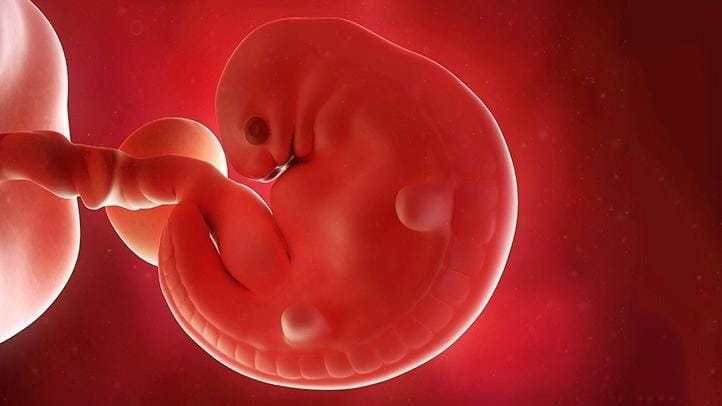

3. Tulang belakang, plasenta, dan otak

Pada sekitar minggu ketiga hingga keenam, bentuk tubuh fetus akan mulai terbentuk. Pada awalnya, akan terbentuk beberapa lapisan sel yang bervariasi. Kemudian sebuah titik kecil yang tersambung pada garis seperti benang akan tumbuh. Itulah awal dari otak dan tulang belakang. Pada saat yang sama, plasenta, tempat tumbuhnya bayi juga terbentuk.

4. Jantung

Yang menggerakkan sel untuk berkembang adalah DNA kita. Setelah enam minggu kehamilan, DNA akan memerintahkan jaringan untuk membentuk jantung. Pada saat itu, jantung kita akan terlihat seperti pusat tubuh yang berbentuk tabung kecil. Jaringan mulai bergerak dan memompa, membuat detak jantung.